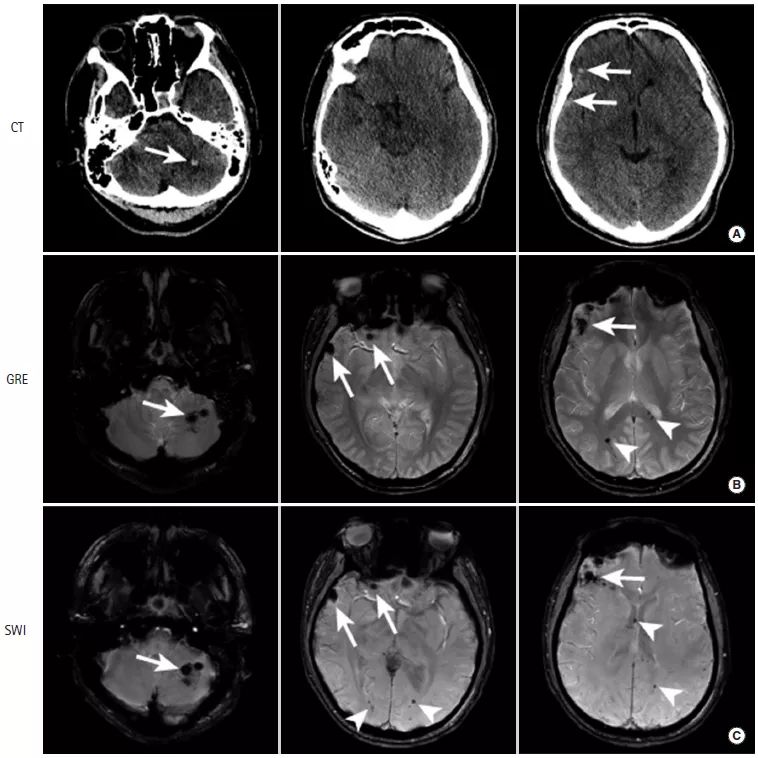

图6

本例患者接受了CT和MRI检查,以评估出血性实质性挫伤。与平扫CT(图A)相比,MRI的GRE(图B)和SWI(图C)序列显示的出血性挫伤(长尾箭头)更为显著。此外,GRE和SWI序列可见脑白质中的脑微出血(三角箭头)。